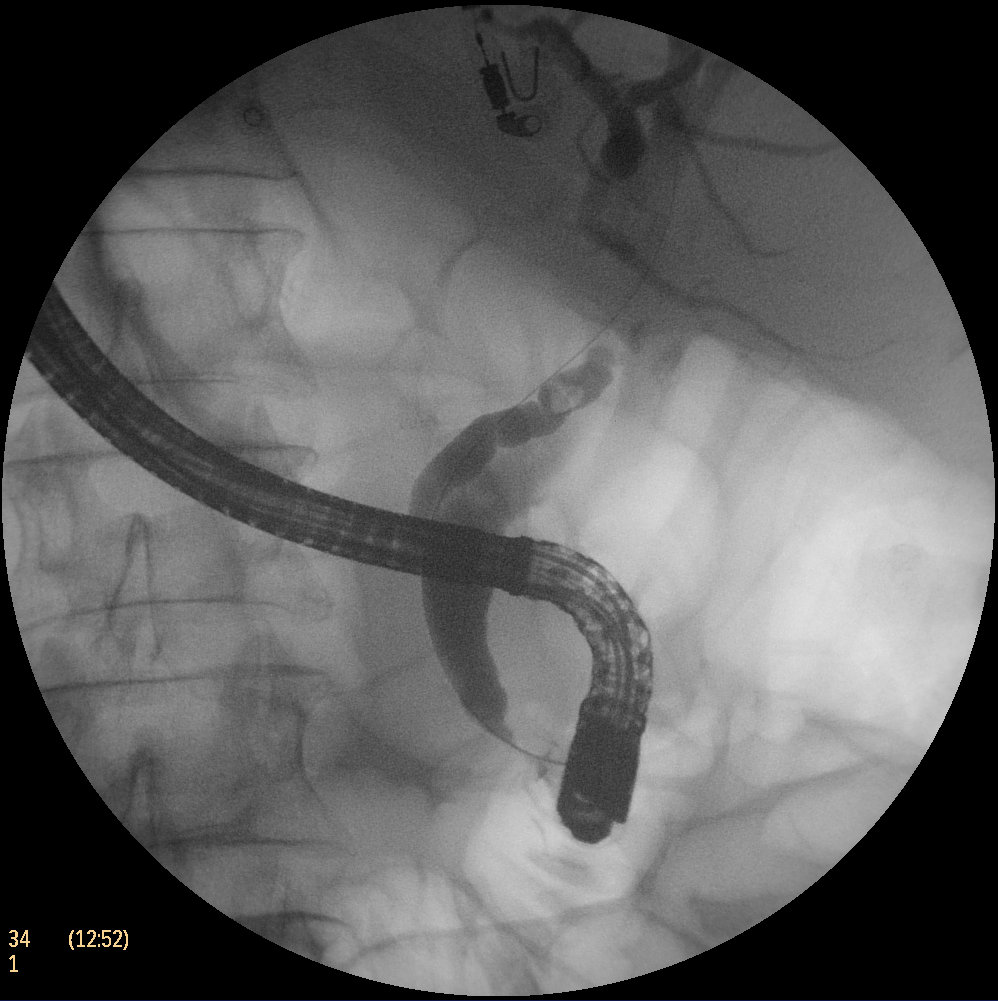

Paciente de 60 años de edad con antecedentes de Situs inversus completo, HTA con FA asociada en tratamiento con Sintrom. Ingresa por el segundo episodio (en 2 meses) de pancreatitis aguda biliar sin criterios de gravedad, apreciándose en la ecografía una vesícula escleroatrófica con dilatación de la vía biliar (hasta 13 mm) e imágenes compatibles con coledocolitiasis de pequeño tamaño en colédoco distal. No se realiza CPRM confirmatoria por padecer claustrofobia. Se decide hacer una CPRE para extracción de las coledocolitasis en posición de decúbito supino con intubación orotraqueal (ITO). La intervención resulta mas difícil de lo habitual por encontrarse la papila en posición opuesta a la normal, con dificultad en el movimiento hacia la derecha del mando L/R del duodenoscopio, que inducía la entrada repetida de la guía en el conducto pancreático. De hecho, dicho conducto tomaba una dirección opuesta a la normal (es decir, hacia las 11 h), mientras que el conducto biliar lo hacía hacia la posición contraria (13 h). Finalmente, tras colocar un stent en páncreas, se realizó una pequeña esfinterotomía de aguja que permitió la canulación biliar y la extracción de las coledocolitiasis con balón de fogarty a 12 mm.

El situs inversus es una anomalía congénita poco frecuente (1:100000 nacimientos) que puede ser parcial o completa. En este último caso, todos los órganos impares se encuentran en lado opuesto (dextrocardia, hígado en hipocondrio izquierdo, etc). Estos individuos tienen una tendencia a malformaciones orgánicas del corazón, grandes vasos y síndrome de Kartagener. Por la alteración anatómica descrita, muchas intervenciones quirúrgicas o instrumentales son mas difíciles de realizar. La CPRE no podía ser menos. El duodenoscopio está diseñado para la posición diestra de la papila, consiguiendo el enfrentamiento correcto con las angulaciones de los mandos U/D y L/R que se pueden realizar normalmente. En los casos de situs inversus completo con la papila y el hígado a la izquierda, si el paciente se coloca en las posiciones habituales (decúbito lateral izquierdo, prono o supino), la CPRE es mas difícil porque la papila se coloca a la derecha y el movimiento en este sentido no tiene la amplitud habitual. Por ello, es necesario apurar la rotación del endoscopio en sentido de las agujas de reloj, usar un papilotomo rotatorio como los autotome de Boston, o bien realizar un precorte que redirija el corte hacia las 12-13 horarias. Hay algún artículo que recomienda realizar la CPRE en decúbito lateral derecho (posición en espejo) para tener toda la movilidad requerida de los mandos en la canulación. Por cierto es el segundo caso realizado con la capturadora médica MediCap USB200 (esa pequeña joya).